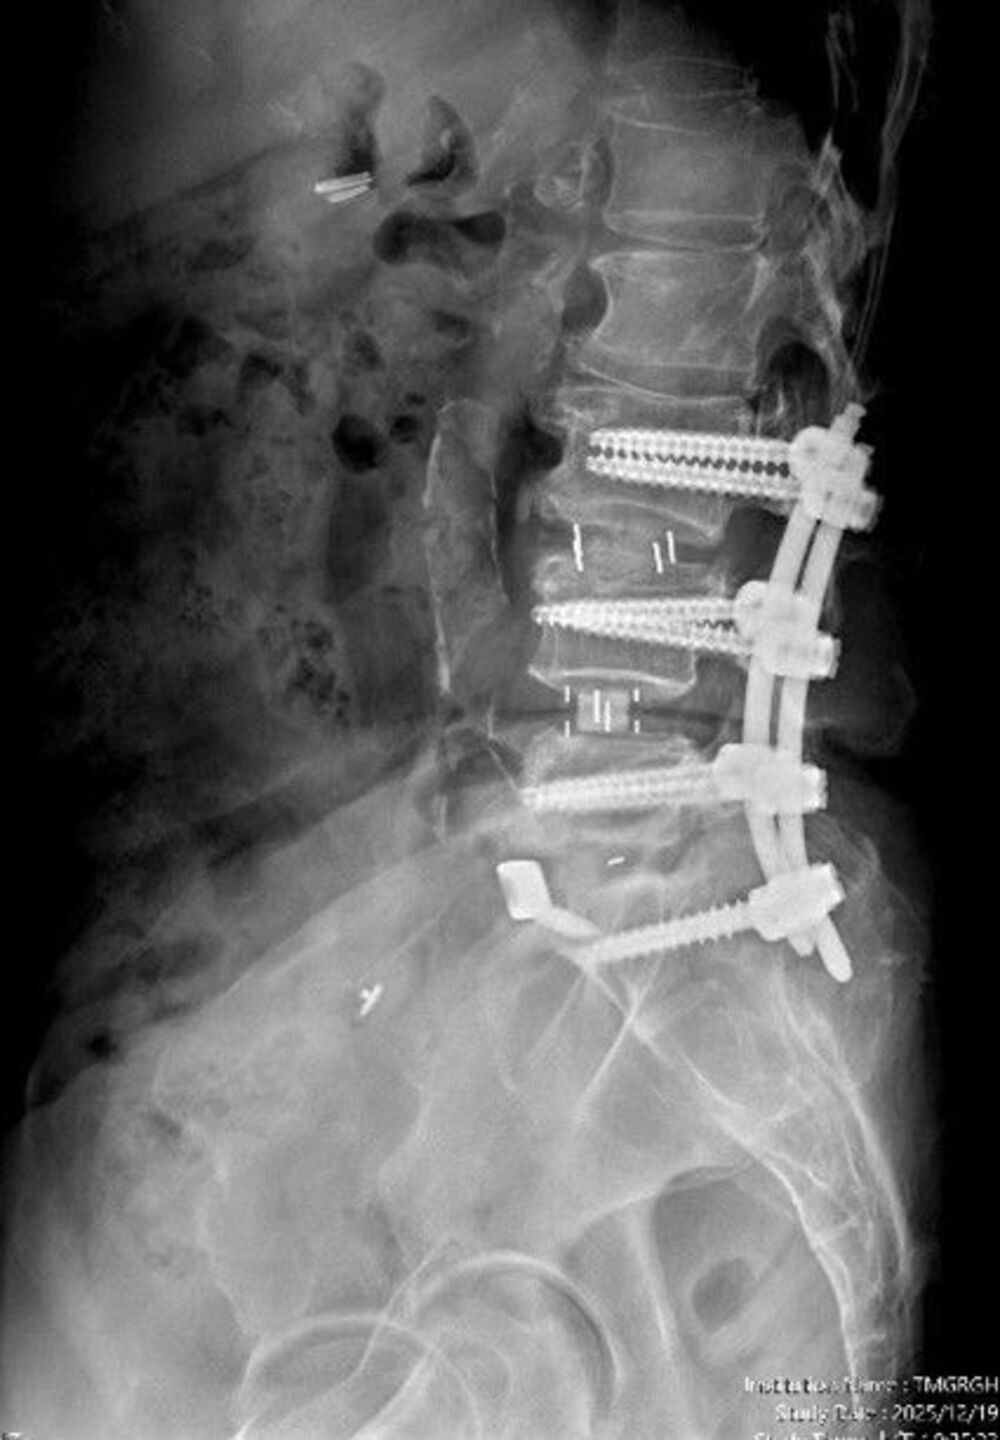

【記者彭勝郎台中報導】一名65歲婦人,長期飽受腰痛、下肢痠麻及坐骨神經痛困擾,行走距離逐年縮短,嚴重影響日常生活品質。經台中市立老人復健綜合醫院骨科部副部長林琮凱醫師詳細檢查後,診斷為第三、四、五腰椎合併第一薦椎多節段脊椎狹窄與神經壓迫。醫療團隊與病患及家屬充分溝通後,決定採用電腦導航輔助之前位/前側位脊椎融合手術,合併後方骨釘固定,一次完成多節段重建。術後病患神經症狀明顯改善,恢復行走能力,生活品質大幅提升。

相較於傳統脊椎手術需分部位分階段進行、住院與復原時間長,中醫大市醫引進的前位或前側位脊椎融合手術,搭配 3D 電腦導航系統,可在同一次手術中完成多節段融合與多部位重建。

手術採間接減壓方式,不需直接進入脊椎腔,大幅降低神經損傷風險。多數病患可於手術當日或隔日配戴背架下床行走,疼痛較少、恢復期明顯縮短,同時提升醫療效能與病患滿意度。